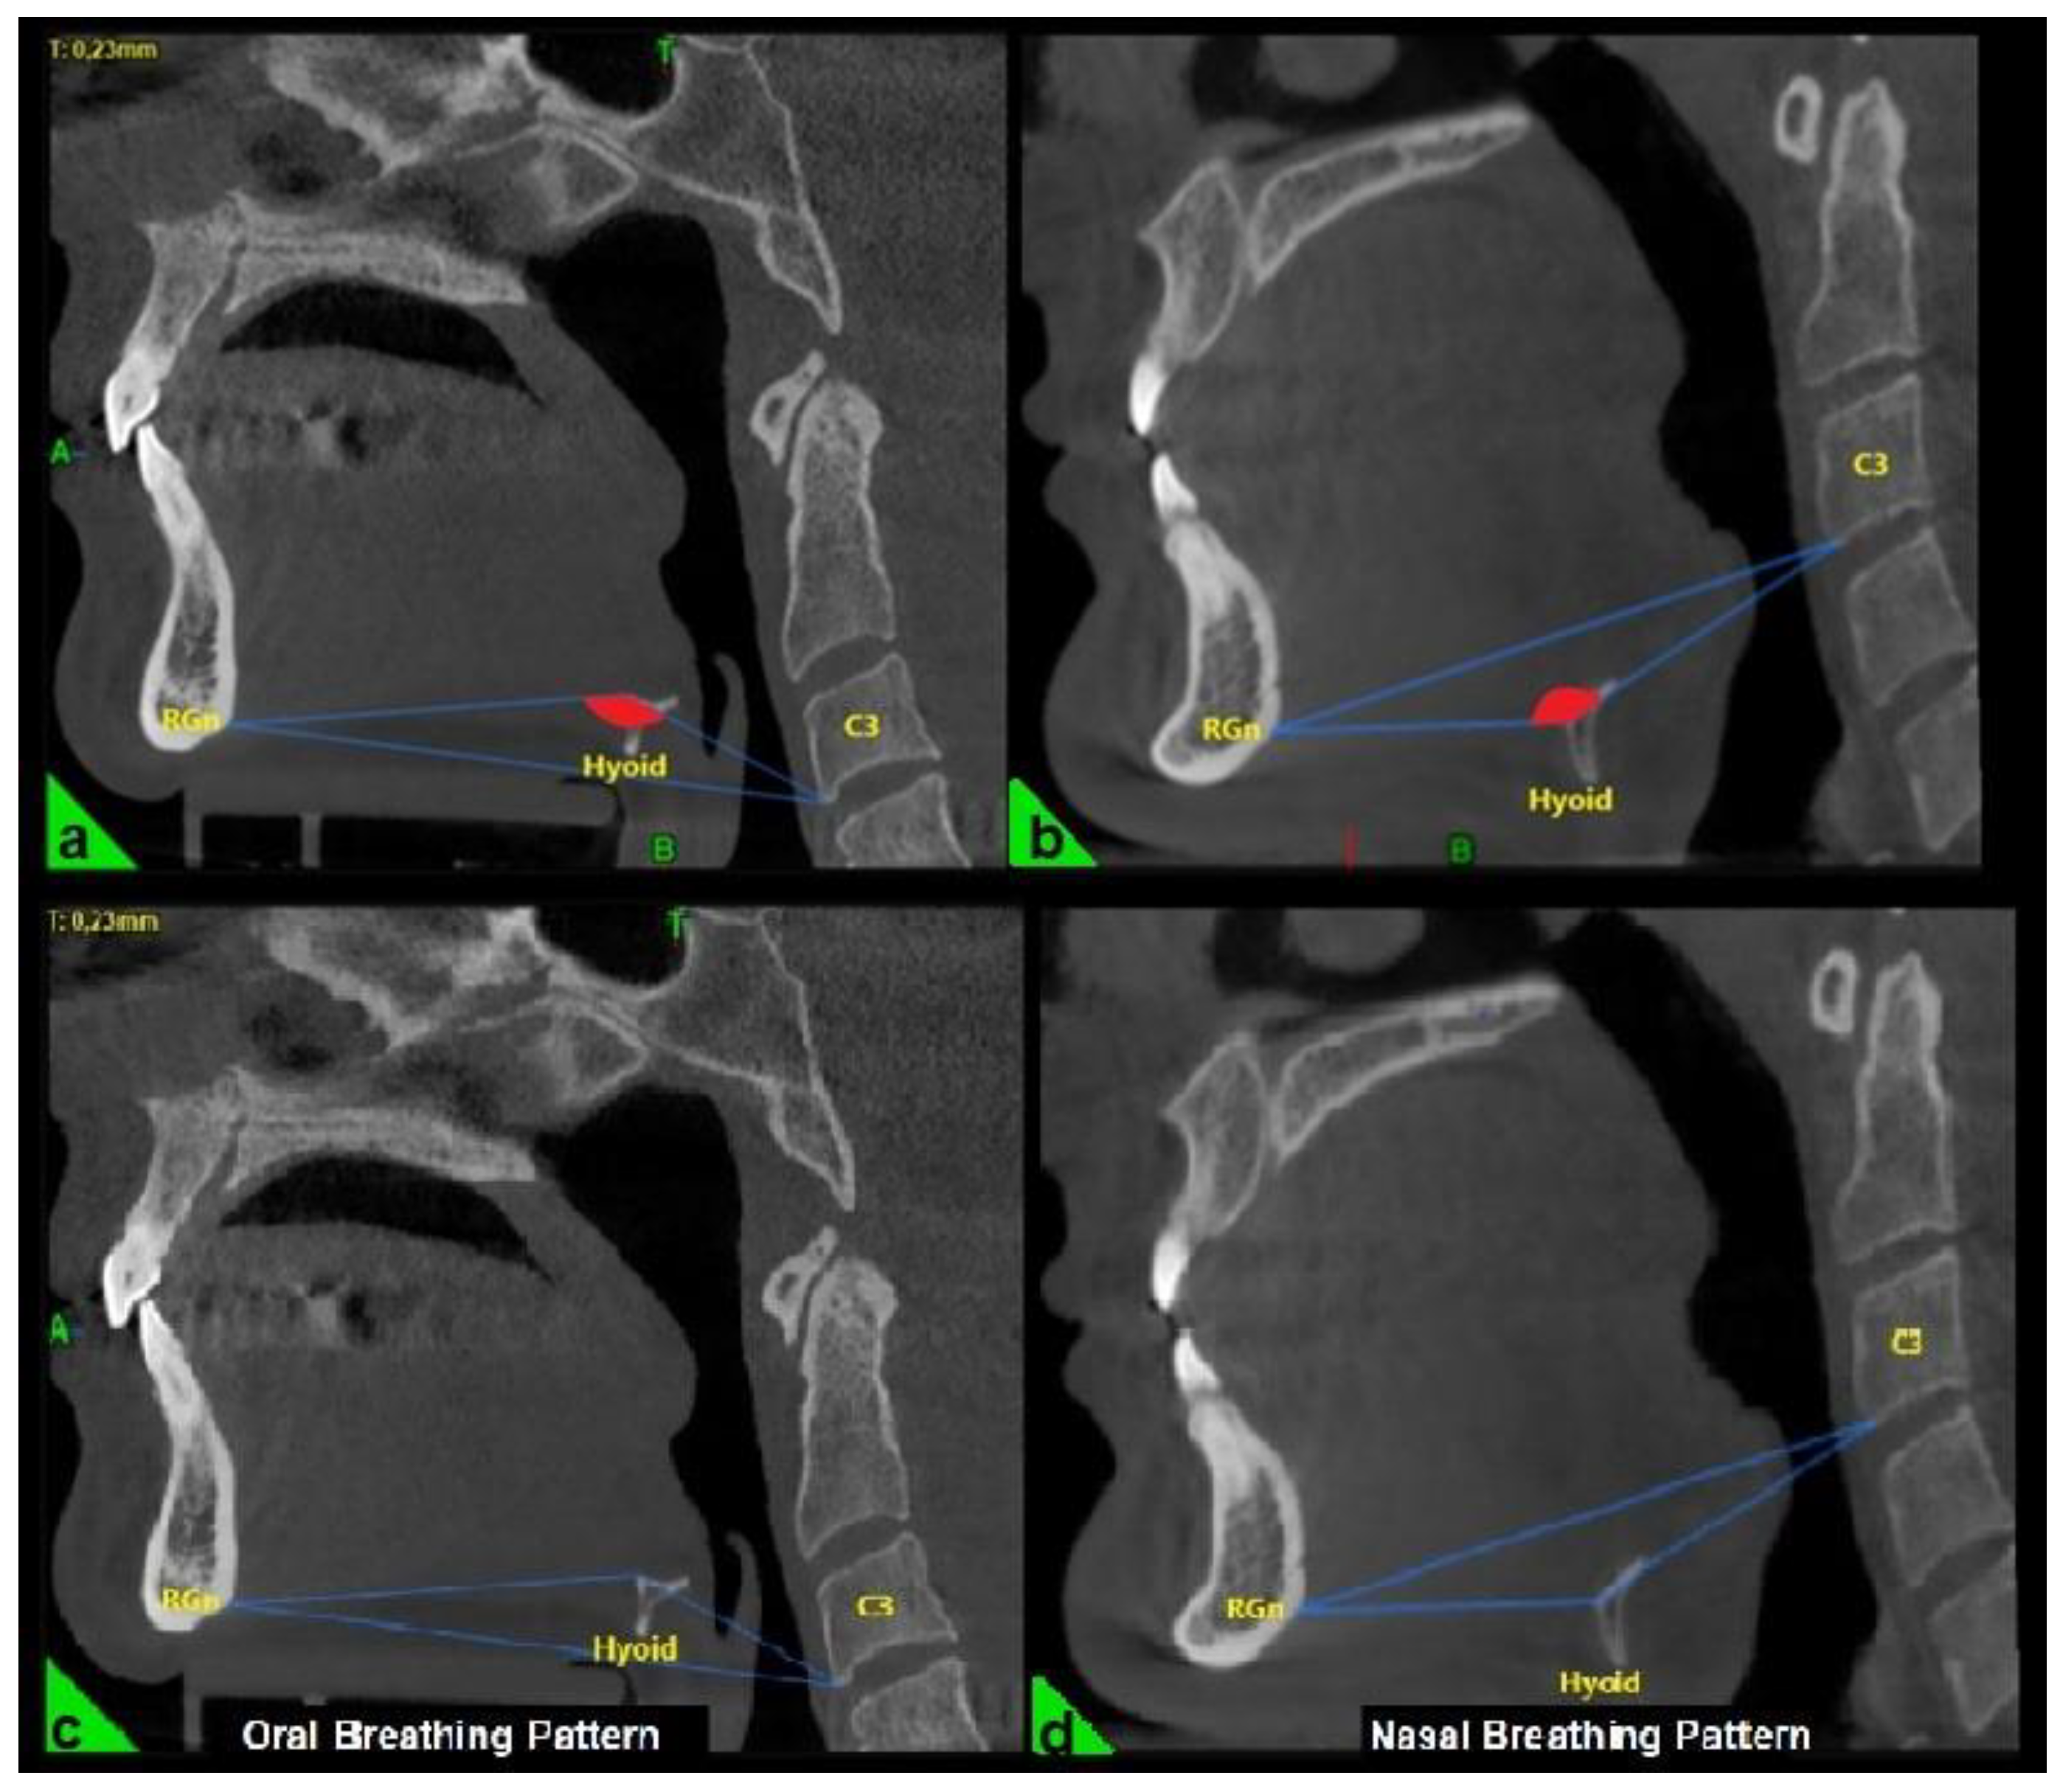

Three-Dimensional Cephalometric Measurements

Participant Grouping Criteria